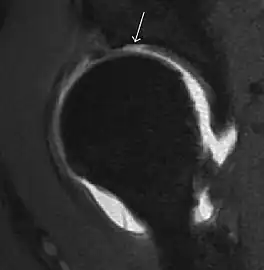

In adults, MRI is currently playing a definite role in the assessment of osteoarthritis. Although traditionally belonging to the arena of radiographs, the role of MRI has been stressed after the term femoral acetabular impingement was coined in 2003. Growing interest has been focused in accurate diagnosis of the acetabular and femoral morphological abnormalities that may lead to early osteoarthritis.[1]

MR imaging is considered paramount to these objectives, mainly when surgery is considered, due to the ability of MRI to portray the whole section of the femoral neck surface, as well as to image the labrum and articular cartilage.[1]

Diagnosis of impingement can only be achieved if, besides imaging findings, there are also clinical symptoms and positive impingement maneuvers.[1]

Most of the angles and measurements described in the plain radiograph section can be accurately reproduced on MRI. In addition, the superiority of MRI resolution with intra-articular contrast allows detection of labral and chondral abnormalities that may influence the choice of medical, percutaneous, or surgical management (Figure 9).[1]

Figure 9:

-

Sagittal T1 weighted image showing anterosuperior labral tear.[1] -

Sagittal T1 weighted image showing chondral lesion.[1] -

Sagittal CT-arthrography showing posteroinferior chondral injury.[1] -

Coronal CT-arthrography (d) showing ligamentum teres tear.[1]

MR arthrography has proven superior in accuracy when compared to native MR imaging. It is considered the best technique to assess the labrum. Knowledge of the normal variable morphology of the labrum helps to differentiate tears from normal variants. A triangular shape is most commonly seen in 66% of asymptomatic volunteers, but round, flattened, and absent labra can also be found in asymptomatic populations. MR arthrography has demonstrated sensitivity over 90% and specificity close to 100% in detecting labral tears. Loose bodies are demonstrated as filling defects surrounded by the hyperintense gadolinium.[1]

Association between labral tears and chondral damage has been demonstrated. This underscores the interaction between cartilage and labrum damage in the progression of osteoarthritis. Chondral damage to the posteroinferior part of the acetabulum as a contrecoup lesion occurs in approximately one-third of pincer cases secondary to persistent abutment on the anterior part of the joint leading to a slight posteroinferior subluxation. This is considered a bad prognosis sign.[1]

MR arthrography can also demonstrate ligamentum teres rupture or capsular laxity, which are debated causes of microinstability of the hip. Elongation of the capsule or injury to the iliofemoral ligament or labrum may be secondary to microtrauma in athletes. MR can demonstrate abnormalities in these cases, such as increased joint volume or a ligamentum teres tear (Figure 9).[1]